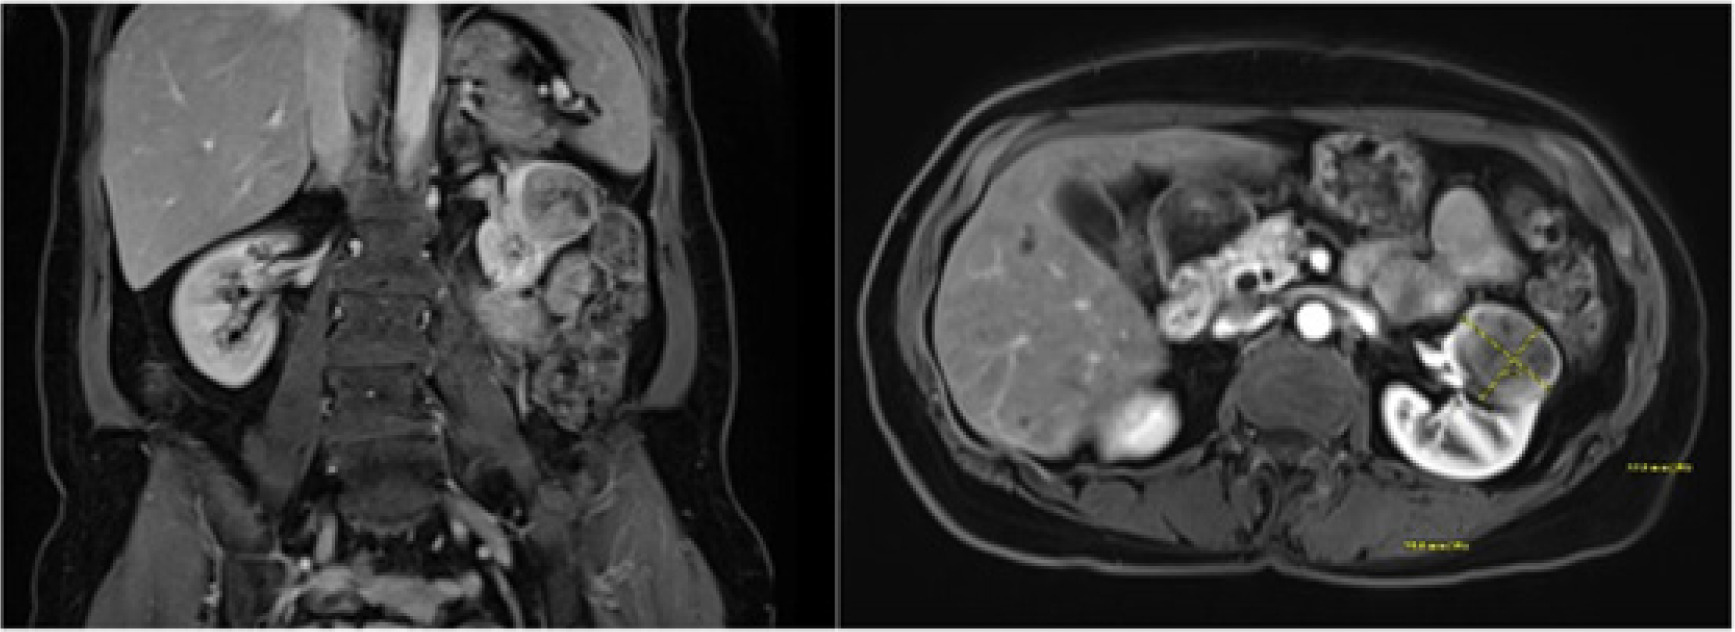

Nine years later, the patient presented to an urgent care with upper respiratory symptoms, including cough, congestion, sore throat, and shortness of breath, for a duration of three 3 days that were refractory to over-the-counter medications. A chest x-ray was negative for airspace disease, but given the history and concern for metastatic disease, CT of the chest was ordered. The patient followed-up with the medical oncology team for review of imaging, which revealed an interval increase in the size of a spiculated lung lesion seen on a CT scan from 2 years prior, enlarged left axillary lymph node, and a new, partially imaged, heterogeneous solid-appearing mass in the anterior cortex of the mid- to upper pole of the left kidney approximately 3.4 × 2.6 cm in size (Figure 1). At that time, MRI of the abdomen (Figure 2) was performed for better characterization of the mass, and PET scan was done which demonstrated hypermetabolic activity in the areas of reference on the CT scan (Figure 3). Referral to interventional radiology was placed for ultrasound-guided biopsies, and left renal mass biopsy was performed. A referral to cardiothoracic surgery was placed for biopsy of an upper lobe pleural nodule, and perihilar cluster of nodules were seen on imaging that were not amendable to ultrasound-guided biopsy. The renal biopsy showed metastatic ACC. Immunostains for CK7, CD117, p40, and SMA were positive, and calponin and PAX8 were negative.

Figure 2: MRI of the abdomen with T1-weighted images in coronal and axial views.